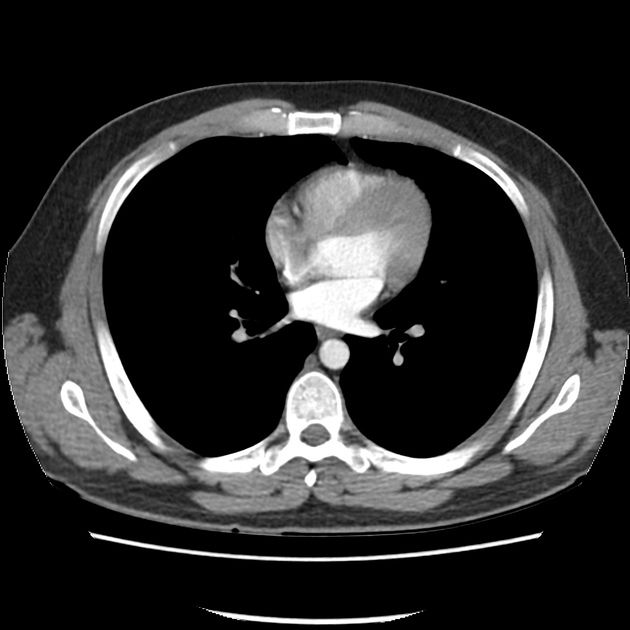

Can you make the diagnosis?

What lesion is indicated by the arrows?